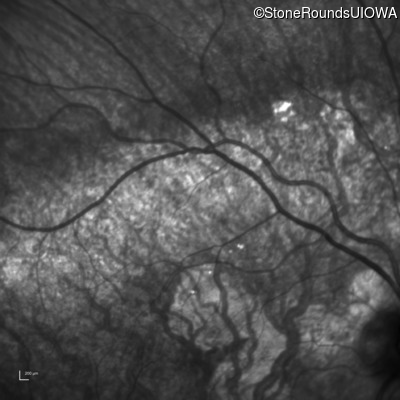

Infrared Fundus Photograph - Left - 20/60 +2 sc

Exemplar